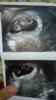

Dziewczyny jestem po wizycie i jestem w ciezkim szoku serduszka bija.

Patrzcie na to Zobacz załącznik 814296

Co? Jest 3?Dziewczyny jestem po wizycie i jestem w ciezkim szoku serduszka bija.

Co? Jest 3?